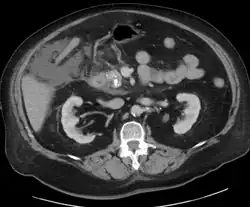

Calcified pancreatic duct stones with some free intra-abdominal fluid

A contrast-enhanced CT scan is usually performed more than 48 hours after the onset of pain to evaluate for pancreatic necrosis and extrapancreatic fluid as well as predict the severity of the disease. CT scanning earlier can be falsely reassuring.